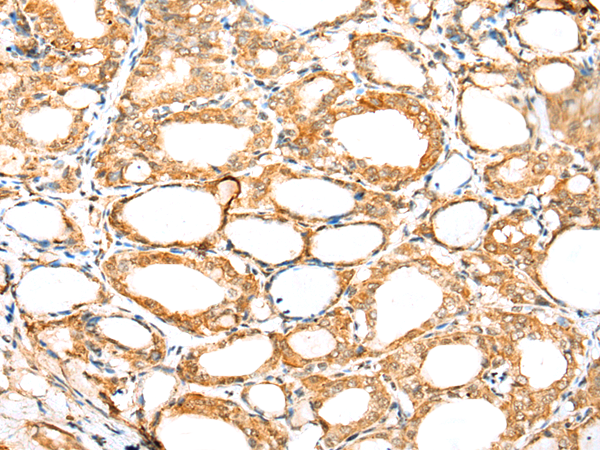

分类: 科研抗体货号: P01960别名: UAP; UBAP; NAG20; UBAP-1应用: IHC反应种属: Human, Mouse, Rat